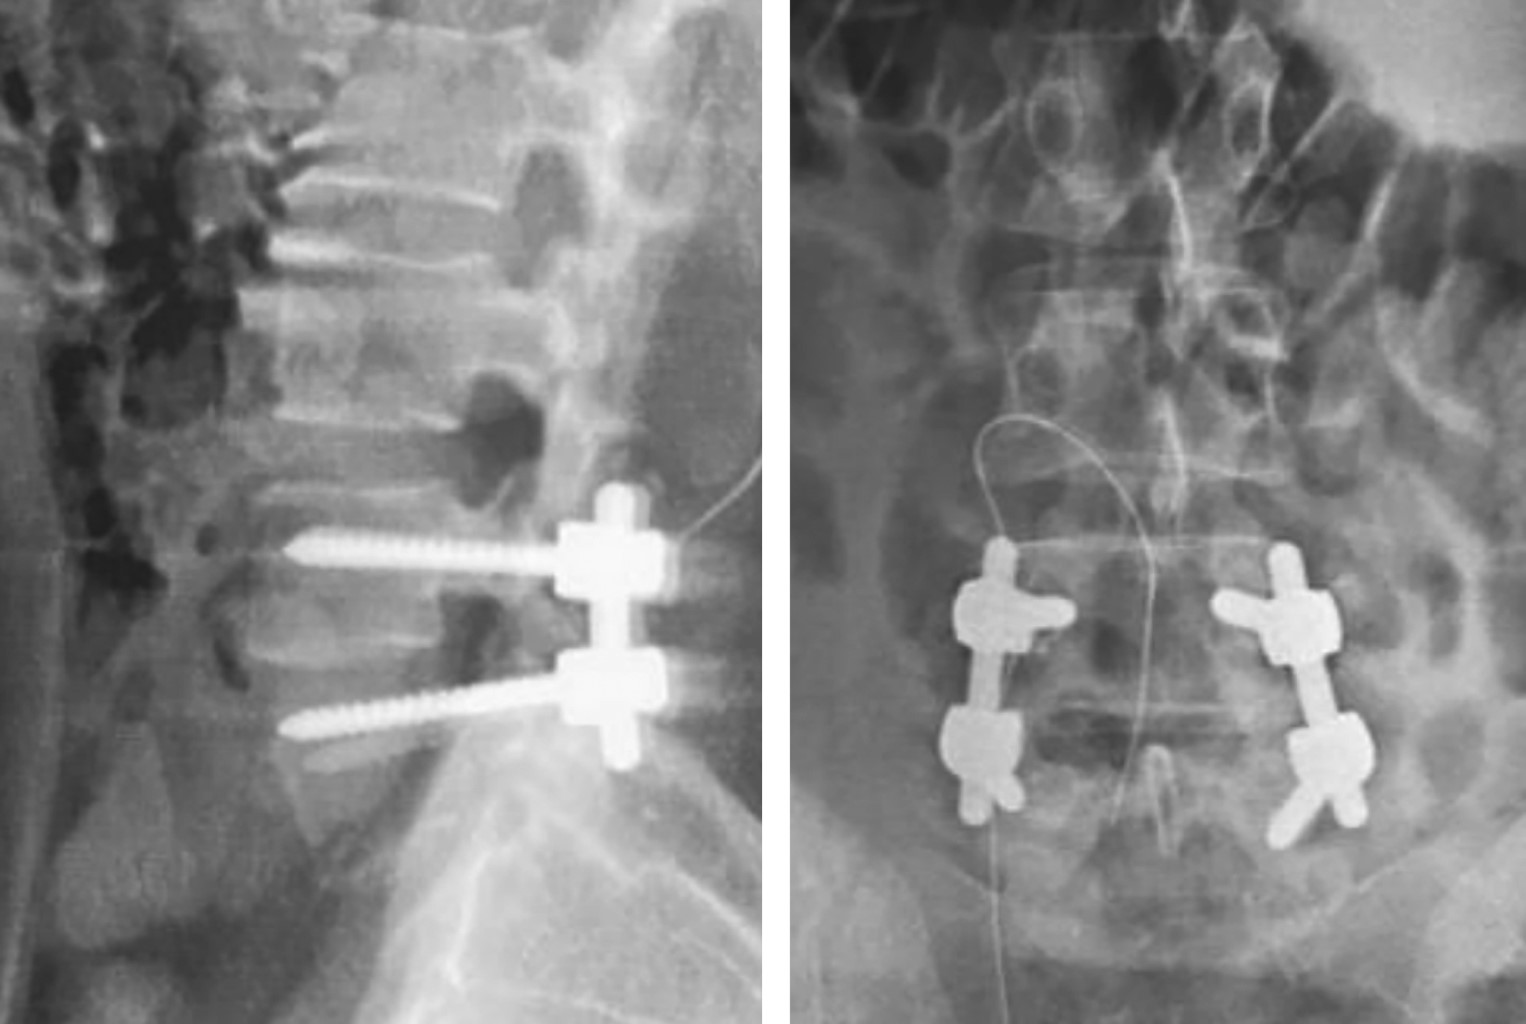

Calcification of the ligamentum flavum is a rare disease that affects mainly elderly women. This calcification is a rare condition in the lumbar spine, different studies conclude that it is more likely to occur in the lower thoracic spine in the first place and in the cervical spine in the second place. The mechanisms of ligament calcification in the lumbar spine are associated with high mechanical stress in this segment, it has been demonstrated that humoral and genetic factors also play an important role for ligament calcification, this suggests that ligamentum flavum calcification is related to alterations in bone metabolism associated with intrinsic factors such as mechanical factors. There are few cases reported in the literature of radicular presentation associated with calcification of the ligamentum flavum in the lumbar spine. In young patients, it may clinically manifest as lumbar myeloradiculopathy. The cauda equina syndrome resulting from compression of the nerve roots consists of lumbar pain, uni or bilateral radicular pain, sensory disorders and alterations in the sexual and/or sphincteric sphere. The most common cause of this syndrome is an extruded disc herniation; however, any lesion that causes compression of the nerve roots distal to the conus medullaris, whether due to tumors, trauma, calcification or ossification of ligament structures and post-surgical complications will result in cauda equina syndrome. We present the case of a 35-year-old female patient with calcification of the ligamentum flavum in the lumbar spine presenting radiculopathy, alterations in sensibility and urinary incontinence. Magnetic resonance imaging showed compression of the cauda equina at L4-L5 on the left side. Decompressive laminectomy of L4 and L5 with resection of the calcified ligamentum flavum was performed. Histopathological findings showed acellular hyaline changes and dystrophic calcifications of the ligamentum flavum. Alterations in sensation and urinary incontinence improved after surgery. The understanding of the external factors, the pathogenesis and the clinical presentation supported by imaging studies guide us to the diagnosis of this rare condition.

Figure 2